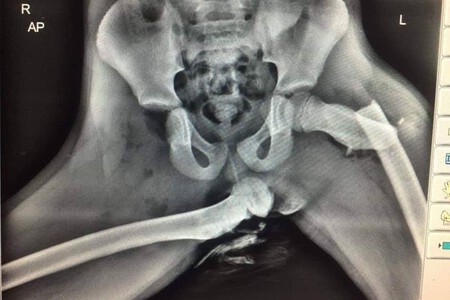

El mensaje de esta imagen fue tan impactante, que pronto se hizo viral: se trataba de una radiografía real que mostraba una pelvis totalmente destrozada tras un siniestro vial. Según explicó el agente, la imagen pertenecía al pasajero de un vehículo que viajaba en el asiento delantero con los pies apoyados en el salpicadero en el momento de la colisión.

“Aquí hay una radiografía de horribles lesiones sufridas en un pasajero del asiento delantero que tenía los pies en el salpicadero en el momento de una colisión”, rezaba la imagen original, que después fue difundida por varios sanitarios de todo el mundo e incluso por la propia DGT.

A tenor de la imagen, el impacto debió ser tan fuerte que la articulación de la cadera derecha acaba rota y el fémur termina desgarrando la piel, posiblemente por el impacto del airbag. Al parecer, la víctima no superaba los 10 años. “Si tu pasajero lo hace, quizá deberías dejar de conducir y enseñarle esto”, sentenciaba entonces el agente Ian Price.